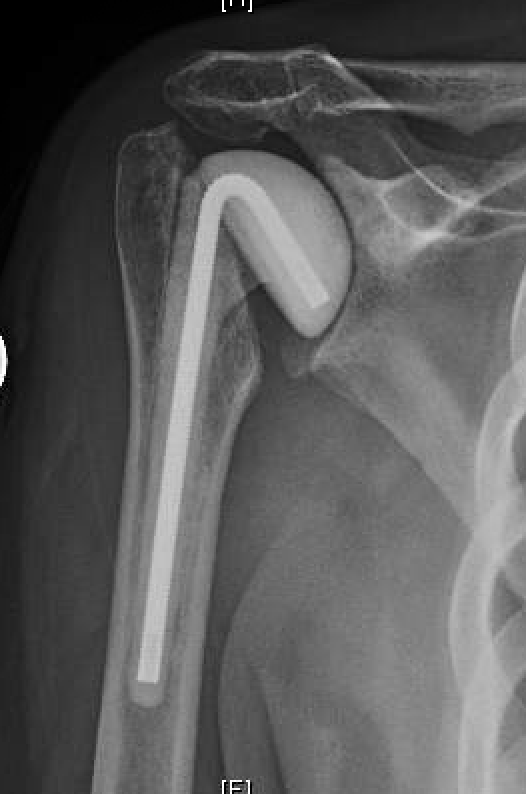

Antibiotic spacer in place after shoulder arthroplasty explantation Download Scientific Diagram How Long Does An Antibiotic Spacer Stay In The implant is thoroughly cleaned, and plastic liners or spacers are replaced. Avoid placing pillow under the knee to prevent hip flexion. In some cases, depending on the severity of the problem,. I’ve had my spacer in for 9 months now. Avoid prolonged sitting, standing, and walking. After the procedure, intravenous (iv) antibiotics are prescribed for approximately 6 weeks. I. How Long Does An Antibiotic Spacer Stay In.

Antibiotic spacer in place after shoulder arthroplasty explantation Download Scientific Diagram How Long Does An Antibiotic Spacer Stay In I had surgery last may and my surgeon and i discussed keeping it in as long as possible. Your antibiotics will be managed by your infectious disease physician, usually for 6 weeks. After the procedure, intravenous (iv) antibiotics are prescribed for approximately 6 weeks. I’ve had my spacer in for 9 months now. The spacers are left in for about. How Long Does An Antibiotic Spacer Stay In.

Grashey view of an antibiotic spacer in same patient after all the... Download Scientific Diagram How Long Does An Antibiotic Spacer Stay In I’ve had my spacer in for 9 months now. Avoid severe pain with exercises. The spacers are left in for about six weeks during which time patients can use a walker or wheelchair to get around. Avoid prolonged sitting, standing, and walking. Avoid placing pillow under the knee to prevent hip flexion. I had surgery last may and my surgeon. How Long Does An Antibiotic Spacer Stay In.

Postoperative radiograph of an antibiotic spacer of the right shoulder... Download Scientific How Long Does An Antibiotic Spacer Stay In Avoid severe pain with exercises. I had surgery last may and my surgeon and i discussed keeping it in as long as possible. The spacers are left in for about six weeks during which time patients can use a walker or wheelchair to get around. The implant is thoroughly cleaned, and plastic liners or spacers are replaced. After the procedure,. How Long Does An Antibiotic Spacer Stay In.